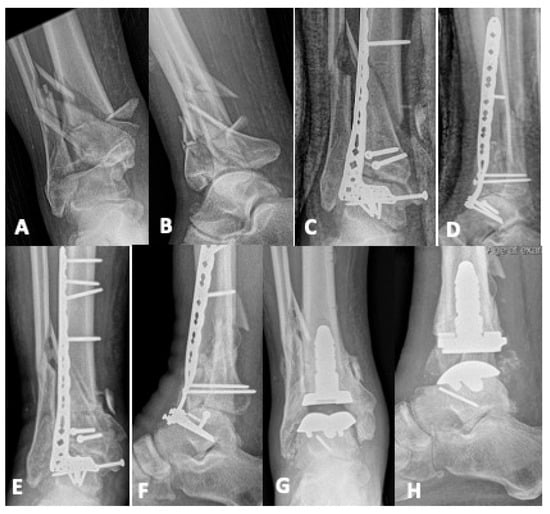

Management Strategies for Failed Pilon Fractures: A Personalized Approach to Revision Reconstruction

Despite advances in staged protocols and fixation techniques, treatment of pilon fractures remains a significant challenge in orthopedic trauma, with up to 21% of patients requiring revision surgery. Management of a pilon fracture that has failed initial treatment involves navigating a myriad of complicating variables, including infection, bone loss, malalignment, and nonunion. Although no single surgical approach can be aptly applied to the broad range of pathology and severity spanned by these patients, this narrative review provides a systematic framework for developing a revision pilon reconstruction plan. We present a protocol for pre-operative assessment and review current techniques for infection eradication, bone defect management, deformity correction, and joint-preserving versus joint-sparing surgery. These fundamental strategies form the foundation of a successful salvage plan and can be personalized to address specific fracture morphology, host factors, and goals of care. Full article

Show Figures

Figure 1